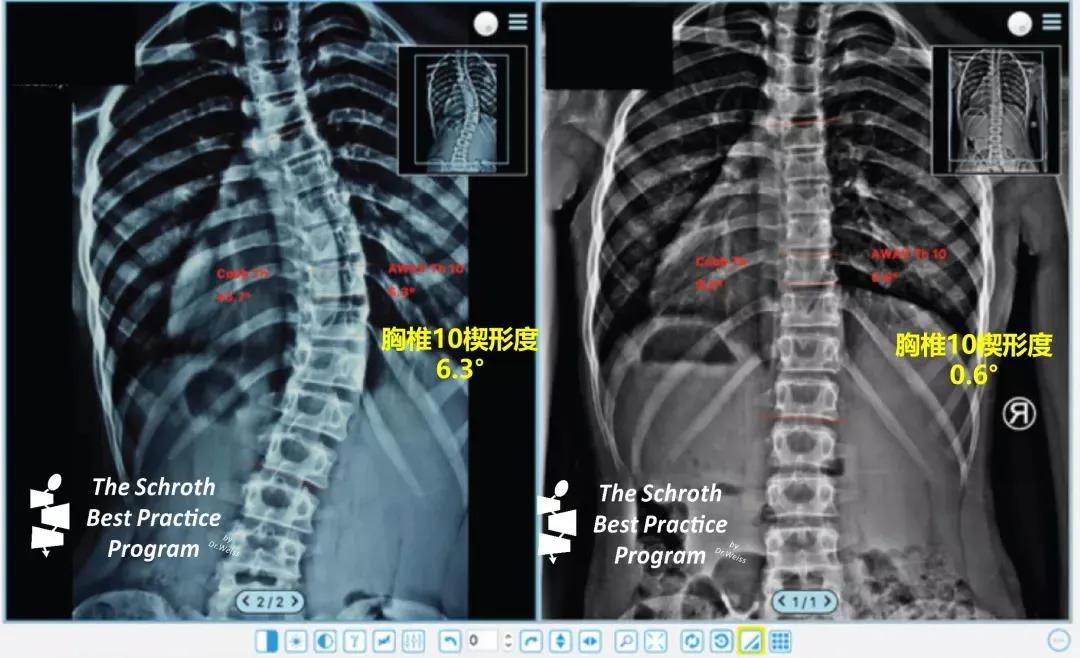

研究方法:我们根据以下纳入标准审查了我们的数据库:诊断为 AIS、Risser 0-2、年龄 10-14 岁且 Cobb 角大于 35°的女孩。我们的研究队列由 27 名符合纳入标准的患者组成,所有患者佩戴施罗斯GBW支具,平均支具佩戴时间为每天 16.6 小时,Cobb 角在 36° 到 79° 之间。我们研究的目标值是顶椎楔形,在支具治疗开始前测量两次,在平均 20.5 个月的治疗随访期后测量两次。楔形的不平衡结构状态的矫正率为 44%。

研究结论:我们的研究支持以下假设:高矫正率的不对称支具可改善骨骼未成熟的 AIS 女孩的椎体楔形程度。